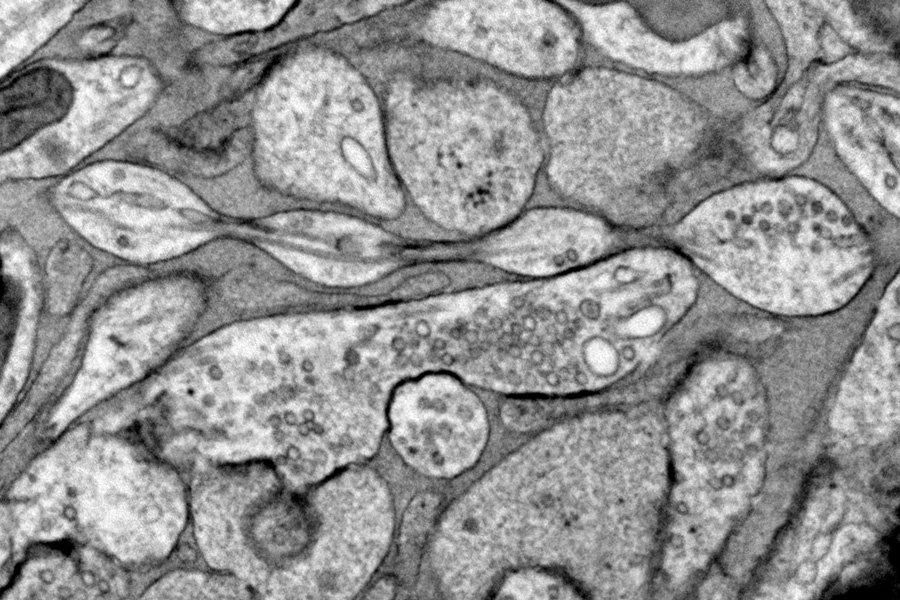

Но Жаклин Грисволд из лаборатории Ватанабе, обнаружила нечто иное в нейронах мышей, сохраненных с помощью техники, называемой заморозкой под высоким давлением. По ее словам, этот метод позволяет сохранить «тонкую структуру очень, очень маленьких частей клеток» лучше, чем химические фиксаторы, обычно используемые в микроскопии. Она применила эту технику как к нейронам мышей, выращенным в чашке, так и к образцам из сверхтонких срезов мозга взрослой и эмбриональной мыши. (Группа изучала подмножество нейронов, которые не миелинизированы, то есть они не обернуты во внешний, изолирующий жировой слой, который может ограничивать форму аксона.)

Используя электронный микроскоп, она заметила равномерно расположенные маленькие жемчужины диаметром около 200 нанометров вдоль аксонов мыши. Капли были меньше и более равномерно расположены, чем стрессовые шарики Летерье, и они ничего не содержали, что предполагает, что они не были результатом клеточных пробок.

Это открытие перекликается с другими: Ватанабе заметила похожие жемчужины аксонов у круглых червей в 2013 году, но не стала исследовать их дальше, а Буркхардт недавно увидела их у гребневиков. Грисволд также говорит, что видела жемчужины аксонов в мозговой ткани человека, обработанной методом заморозки под высоким давлением, хотя она и ее коллеги еще не опубликовали это открытие.